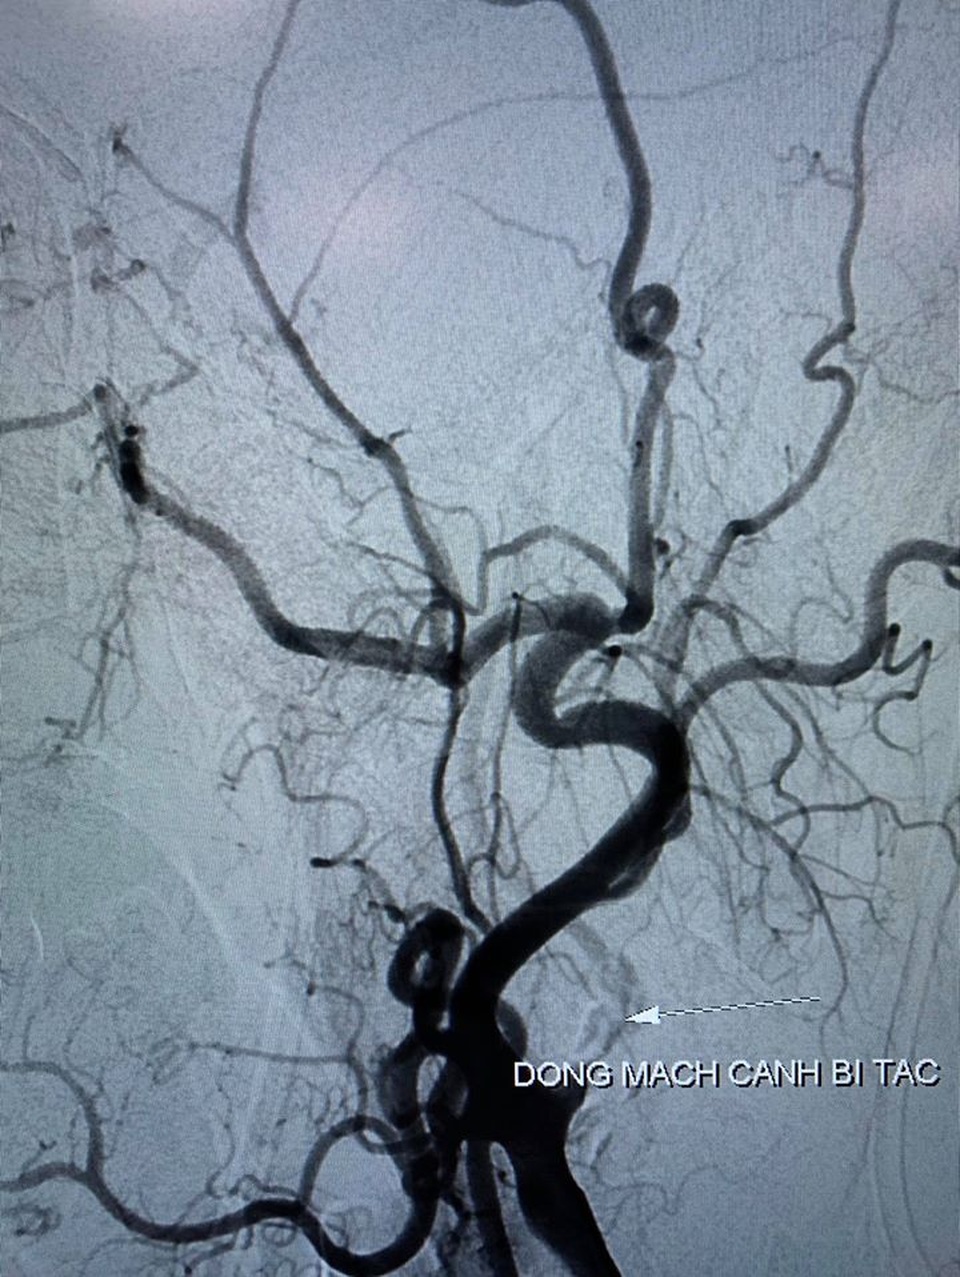

Nữ bệnh nhân Đinh Thị C. (63 tuổi, ngụ tại Sóc Trăng) đến bệnh viện Đột Quỵ Cần Thơ trong tình trạng nguy kịch. Qua khai thác bệnh sử bác sĩ ghi nhận, 4 giờ trước khi nhập viện, nữ bệnh nhân có biểu hiện yếu liệt nửa người bên phải, lơ mơ, không nói được. Kết quả chiếu chụp cho thấy, bệnh nhân bị tắc động mạch não giữa bên trái, có tổn thương não. Các bác sĩ quyết định can thiệp cấp cứu lấy huyết khối động mạch não, tái thông mạch máu cho người bệnh. Sau can thiệp, bệnh nhân đã bình phục tốt, tri giác ổn định, vận động được chân tay.